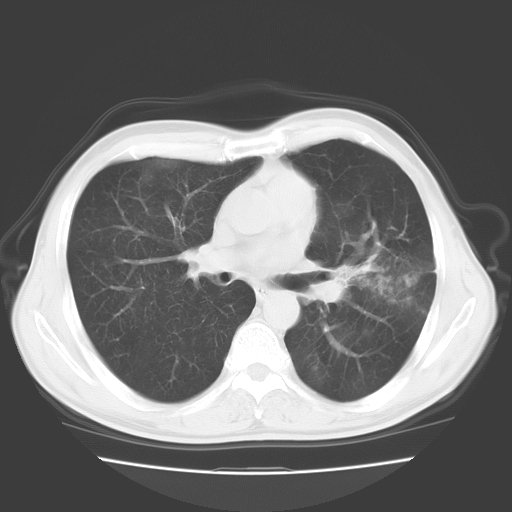

以下是引用随光逐影在2008-11-20 23:02:00的发言:[br]1)考虑左肺上叶周围型肺癌可能性大。2)两肺散在性肺泡积血。[br][br][本贴已被 随光逐影 于 2008-11-20 23:09:31 修改过]

以下是引用drzhang8888在2008-11-20 22:20:00的发言:[br]密集的短毛刺,血管集束,胸膜凹陷,周边型肺癌可能性大,另双肺多发磨玻璃影,考虑感染

以下是引用流浪星在2008-11-20 22:28:00的发言:[br]左肺上叶近外围区见一类圆形结节影,毛刺征、胸膜尾征阳性,临近肺组织见多发渗出灶。考虑1,炎症性病变。 2.周围性肺癌。建议抗炎治疗后复查。

以下是引用qc80012345在2008-11-21 5:53:00的发言:[br]支持;周围型肺癌诊断。增强扫描。